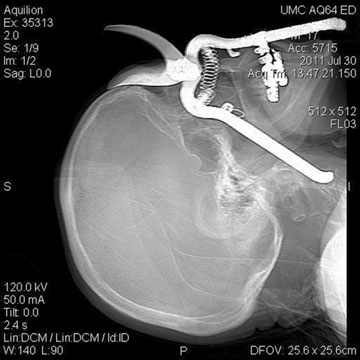

Green Valley man survives shears impaled in skull [Arizona Daily Star, via Nerdist]

Warning: Garden Shears Not for Pruning Human Face